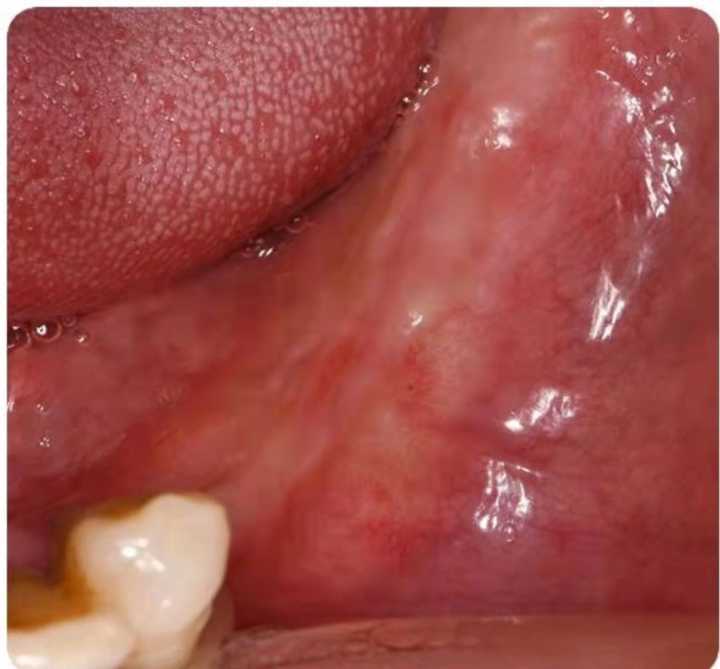

下面這組案例,種植牙修復(fù)冠破損,拆卸后,頸部有一片粘接劑。

激光筆照射后,發(fā)出粉色熒光,這說(shuō)明有細(xì)菌感染。粘接劑殘留,是一個(gè)嚴(yán)重的菌斑滯留因素。一般的種植醫(yī)生不懂修復(fù),可能會(huì)出現(xiàn)這種問(wèn)題。

可以用口內(nèi)粘結(jié)代型法降低風(fēng)險(xiǎn),或者口外粘接。